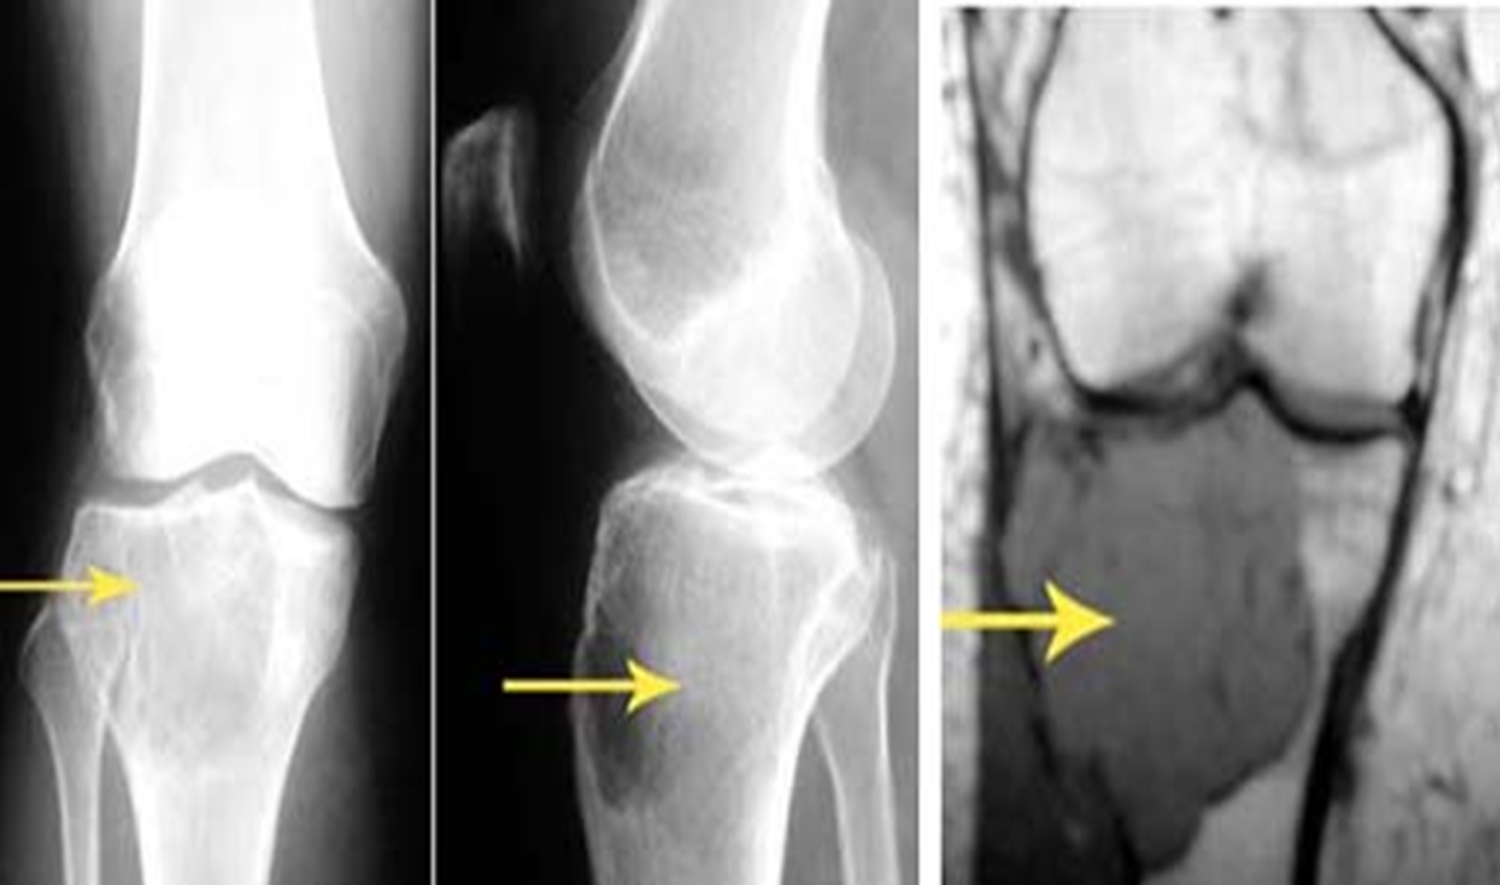

Adult patient: Giant cell Tumor. Expansile lytic lesion eccentric location The subarticular position is characteristic of this tumour.

Adult : Expansile lytic lesion, eccentric in the metaphysis. Sub articular surface May violate the cortex . Aggressive nature